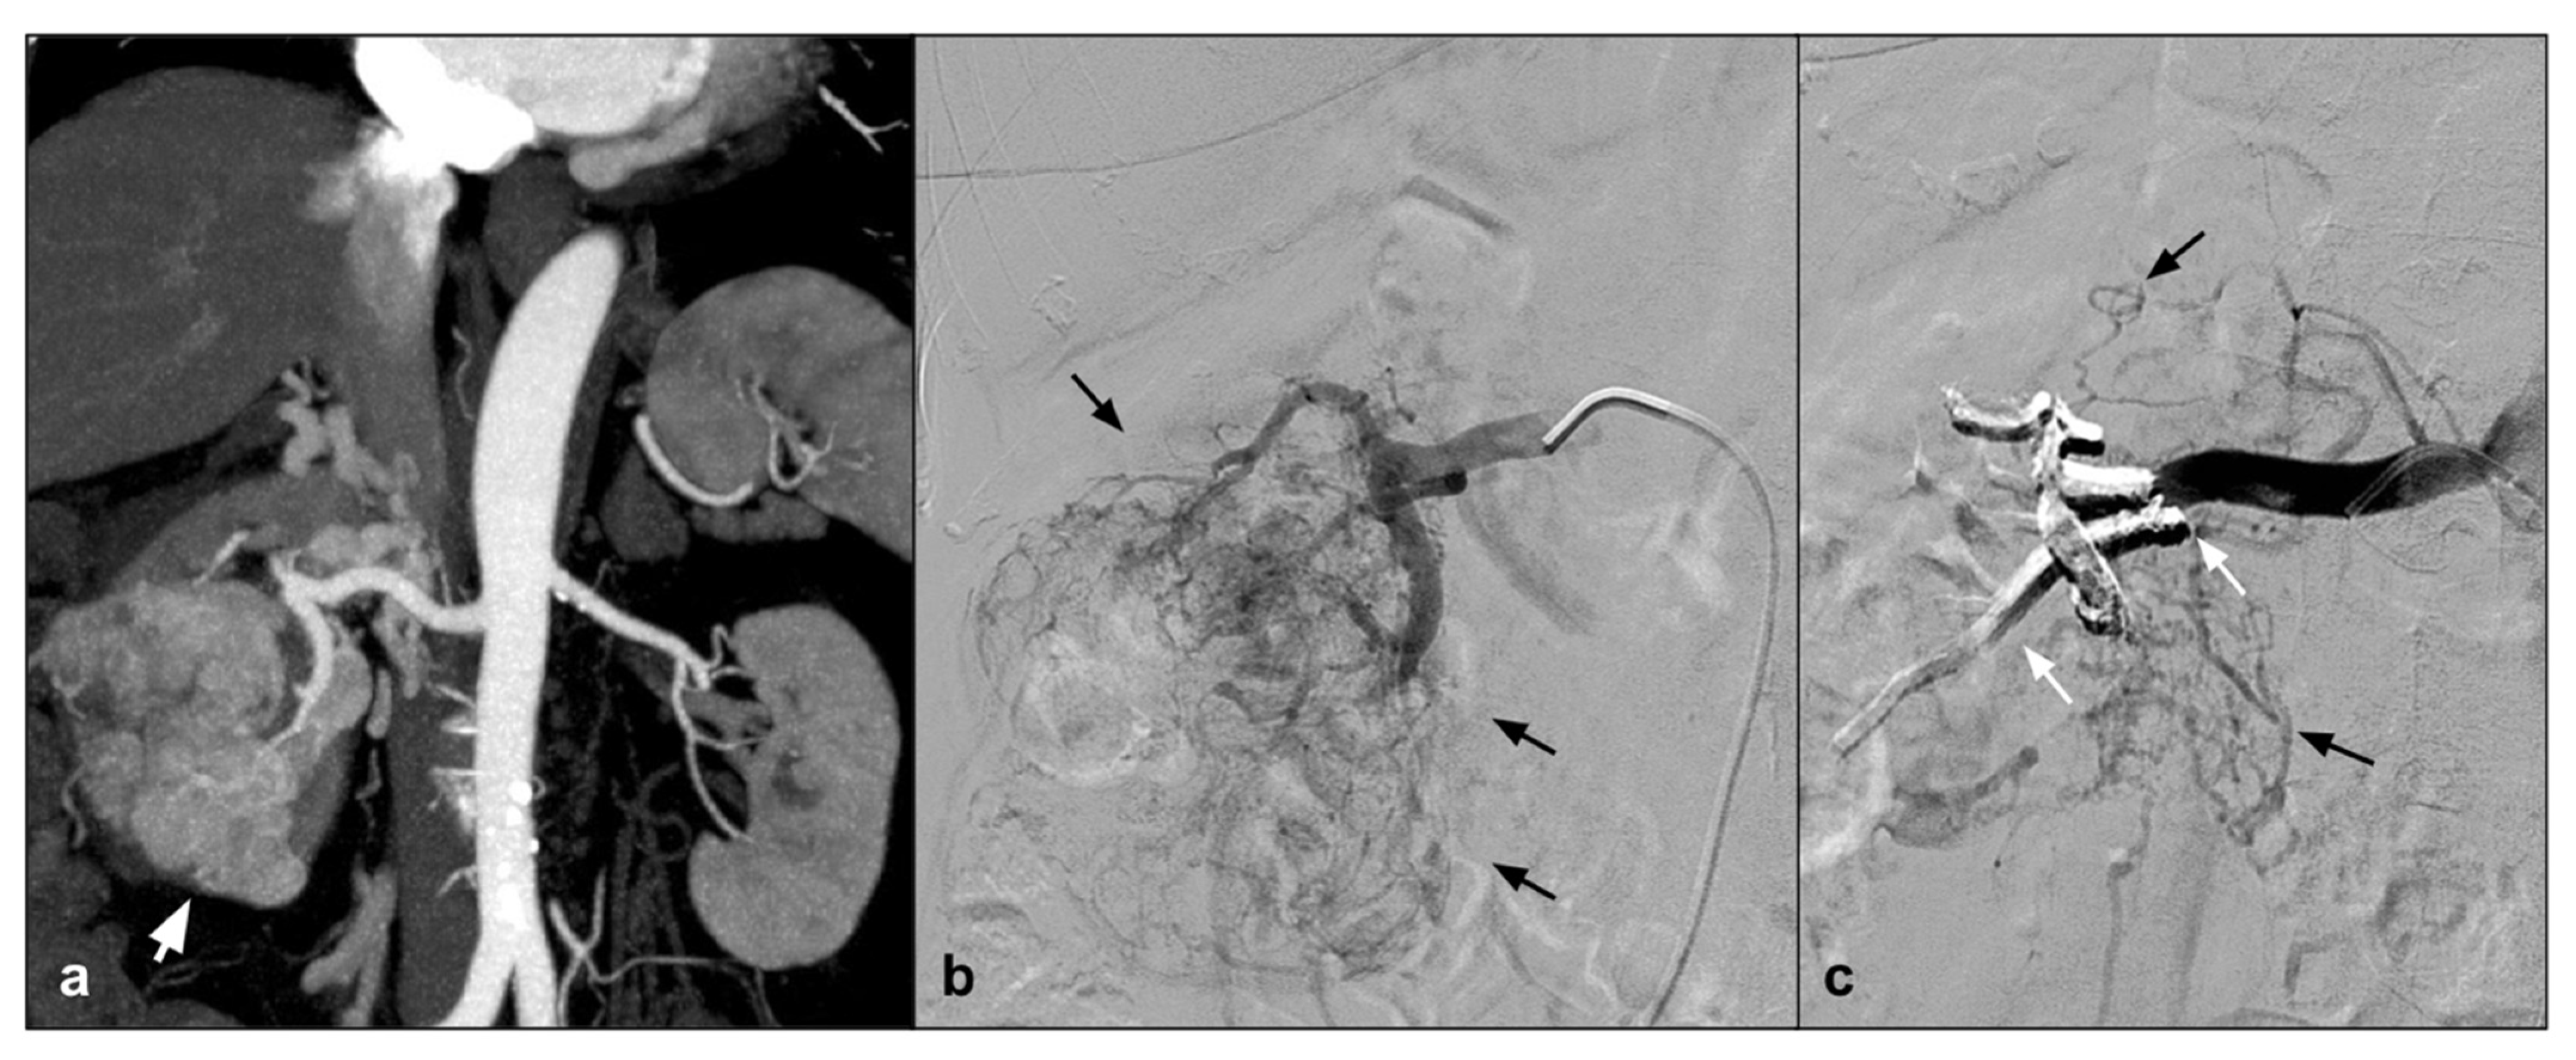

In addition to the peripheral district, which is perhaps the best represented in the literature, we can certainly talk about the uterine district, which is very well represented in literature; however, if we exclude emergency procedures and vascular malformations, the results refer to a few isolated experiences. In particular, the NALEAs are mentioned in a few papers with a single case series. AVM is a quite rare but potentially cause hemorrhages that can be life-threatening (Figure 1) [36].

Figure 1.

(a). Coronal CEMRA MIP demonstrates the presence of voluminous AVM originating from the right uterine artery with aneurysmal venous outflow (white arrows); (b) DSA performed with a vertebral shape catheter in the ipsilateral hypogastric artery confirms the presence of the AVM highlighting the “nidus” (black arrows); (c) single-shot post-treatment fluoroscopy shows the inferior uterine artery treated (white arrow) with coils (not directly tributary of the AVM) and the presence of a cast of Squid 12 at the level of the middle and inferior uterine artery which were the arterial feeding vessels of the AVM (black arrows); (d) post-procedure DSA demonstrates the complete exclusion of the treated AVM (asterisk).

Uterine AVMs are most commonly observed after pregnancy that occurs in women with a past history of induced abortion, curettage, uterine surgery, cesarean section, and diethylstilbestrol exposure. However, there is no consensus as to the type of embolization technique and the type of embolic agent. In this regard, several embolic agents have been used including particles, absorbable gelatin sponge, glue, and metallic coil [37]. The first work is that of Barral with a population of 12 patients, using Onyx as an embolizing agent, with excellent results. In this study, it is highlighted how EVOHs are ideal in the tortuosity of the uterine vessels in case of AVM. In addition, two pregnancies are reported after embolization with Onyx [36]. Another work in which some cases of uterine AVM are cited is the review by Venturini et al., in which Squid is used as an embolic agent, with excellent results [13].